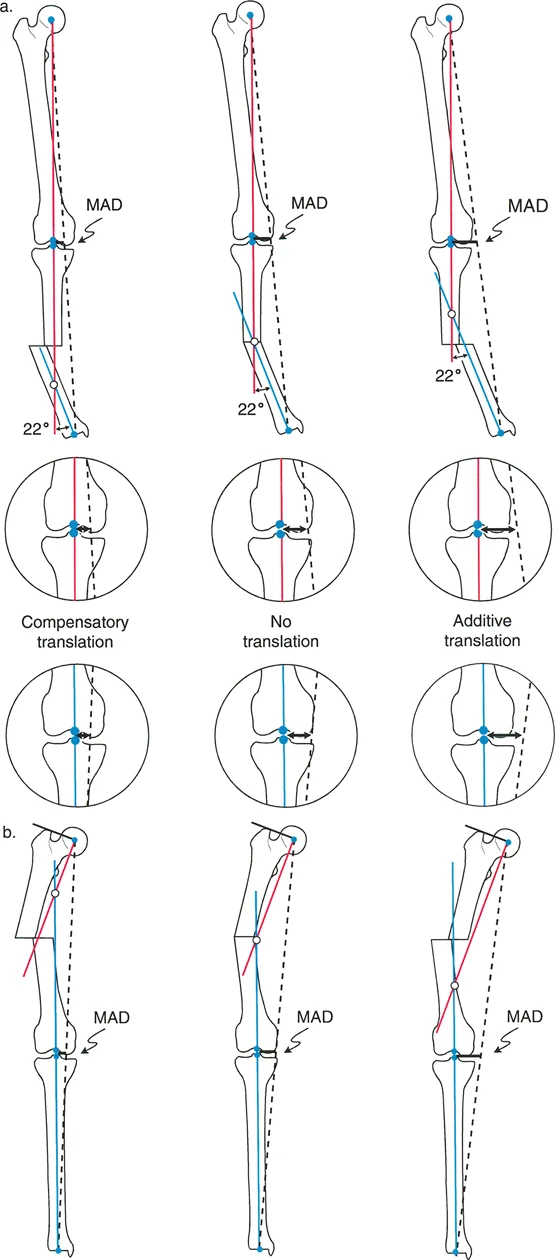

يهدف هذا الدليل الشامل إلى تبسيط هذه المفاهيم المعقدة، وتحويل النصوص الطبية المتخصصة إلى معلومات عالية الأهمية وقابلة للتطبيق سريريًا للمرضى وأسرهم. سنستكشف كيفية قياس هذه التشوهات بدقة، وكيف تتفاعل لتؤثر على المحور الميكانيكي (تأثيرات تعويضية مقابل تراكمية)، وكيفية تحليل تشوهات الانحراف-الانزياح من النوع الأول (التي تحدث في نفس المستوى) للعثور على القمة الحقيقية للتشوه.

- تقييم انحراف المحور الميكانيكي (MAD): يُحسب مدى انحراف المحور الميكانيكي عن مركزه الطبيعي في الركبة.

قياس الانزياح بوجود انحراف

بينما يُعد قياس الانزياح الخالص أمرًا بسيطًا (المسافة العمودية بين خطين متوازيين)، يصبح الأمر أكثر تعقيدًا عند وجود انحراف زاوي، حيث لم تعد خطوط المحور متوازية بل تتقاطع.

وفقًا لمبادئ الدكتور بالي، هناك طريقتان أساسيتان لقياس حجم الانزياح في وجود تشوه زاوي، وكلاهما يتطلب رسم خطوط المحور الوسطي للعظم (mid-diaphyseal axis lines) للجزء القريب والبعيد من العظم.

طريقة المرجع القريب (The Proximal Reference Method):

- في هذا النهج، يُقاس الانزياح كمسافة عمودية من خط المحور القريب إلى خط المحور البعيد، وتُقاس تحديدًا عند مستوى الطرف القريب من الجزء البعيد (موقع الكسر أو قطع العظم).

- لماذا هي مفضلة سريريًا؟ تُفضل هذه الطريقة بشكل كبير، خاصة عند وجود قصر في الطرف. إذا تم الإشارة إلى القصر بالنسبة لخط المحور القريب، فإن مقدار الانزياح المقاس يظل ثابتًا بغض النظر عن مقدار تقصير أو إطالة الطرف. يعمل الجزء القريب كنظام إحداثيات ثابت، مما يجعل هذه الطريقة قوية رياضيًا أثناء التخطيط قبل الجراحة لإطالة العظام أو تصحيحها.

طريقة المرجع البعيد (The Distal Reference Method):

- بدلاً من ذلك، يمكن قياس الانزياح كمسافة عمودية من خط المحور البعيد إلى خط المحور القريب، وتُقاس عند مستوى الطرف البعيد من الجزء القريب من العظم.

- التحدي: على الرغم من صحتها هندسيًا، تُدخل هذه الطريقة متغيرًا مربكًا: طول الطرف. إذا كان هناك قصر محوري، واستخدمت المحور البعيد كنقطة مرجعية، فإن حجم الانزياح المقاس سيتغير اعتمادًا على درجة القصر. يحدث هذا لأن المحور البعيد منحرف بالنسبة للمحور القريب؛ فكلما حركت الجزء البعيد باتجاه القريب (تقصير)، تتغير المسافة العمودية بين المحورين في موقع الكسر.